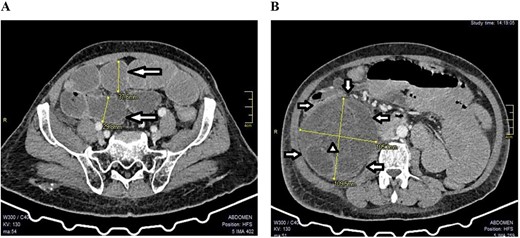

A 73-year-old male, a known patient of adenocarcinoma of the rectum for 1 year, who had undergone neoadjuvant radiotherapy and chemotherapy a year prior and got lost to follow-up, presented at our hospital with a 2-day-history of exacerbated colicky peri-umbilical and right-sided non-radiating abdominal pain, with associated progressive abdominal distension, aggravated by feeding. These were preceded by 2 weeks of difficulty in passing stool and gas (that could be temporarily relieved by the use of the laxative, bisacodyl), nausea and vomiting, initially bilious then overt fecal contents, loss of appetite and generalized body weakness. Two weeks before admission to our hospital, he had been managed nonoperatively for ‘appendicitis’ at a peripheral health facility without improvement, hence the referral. He had no history of any previous surgeries. Physical examination at admission was remarkable for a moderately distended abdomen with marked peri-umbilical and right iliac fossa tenderness, with reduced bowel sounds. On digital rectal exam, the rectum was empty with a tipped polypoid mass high up, ~8 cm from the anal verge. A contrasted abdominal computed tomography (CT) scan was done, which reported features of small bowel obstruction, rectal neoplasm with local metastases to the prostate and urinary bladder and mild pleural effusion with bilateral basal consolidation (Fig. 1).

A CT scan showed features of intestinal obstruction around the paracecal site with dilated small bowel loops; (A) the various dilated small bowel loops (arrows) can be seen; (B) the hernia sac (arrows) with dilated bowel loops inside (arrow head) were seen around the cecum (axial images).